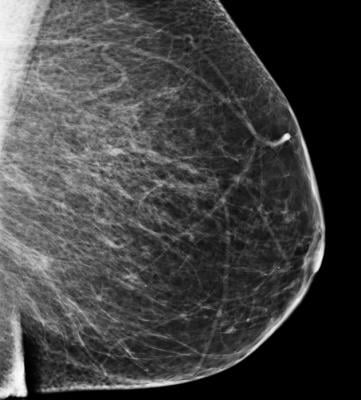

The MSP is open for all women in Germany over the age of 50. It can help detect and therefore treat breast cancer at an early stage. However, because not every screening delivers a clear outcome, mistakes can sometimes lead to false diagnoses, overtreatment, or stress. Spallek said, “That is why every woman should take care to find out about the risks and the benefits before accepting the invitation to attend mammography screening.” The researchers have studied how much women know about the screening and how they then decide in favor of or against it.

Breast cancer is the most frequent type of cancer among women. Early diagnosis through MSP can help to lower the mortality rate. Every two years, women aged between 50 and 69 years are invited to attend MSP. Nonetheless, there is controversy over whether the potential disadvantages of screening possibly outweigh the advantages. This is why the concept of 'informed choice' has become increasingly more important in the health sciences. It states that whoever has sufficient knowledge about a proposal can form her own opinion about it and make a conscious choice.